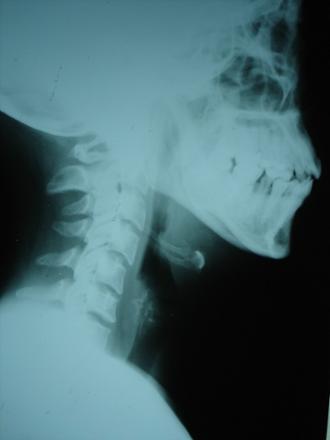

Fractura craneal que comunmente en el fútbol afecta a la zona maxilar (mandíbula) y malar (pómulo).